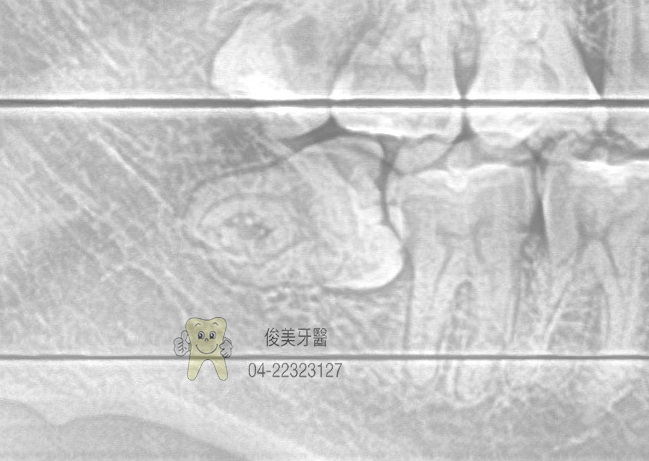

患者的智齒為水平生長,只露出一角,但塞東西後很難清潔,所以決定拔除。

因牙齒埋在骨頭裡,拔除後就會有一個窩洞,需強力冰敷三天,幫助止血、消腫和穩定血塊,並注意傷口清潔。